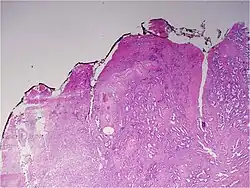

Gleason pattern 3. H&E stain.

• Pattern 3 – The tissue still has recognizable glands, but the cells are darker. At high magnification, some of these cells have left the glands and are beginning to invade the surrounding tissue or having an infiltrative pattern. This corresponds to a moderately differentiated carcinoma.